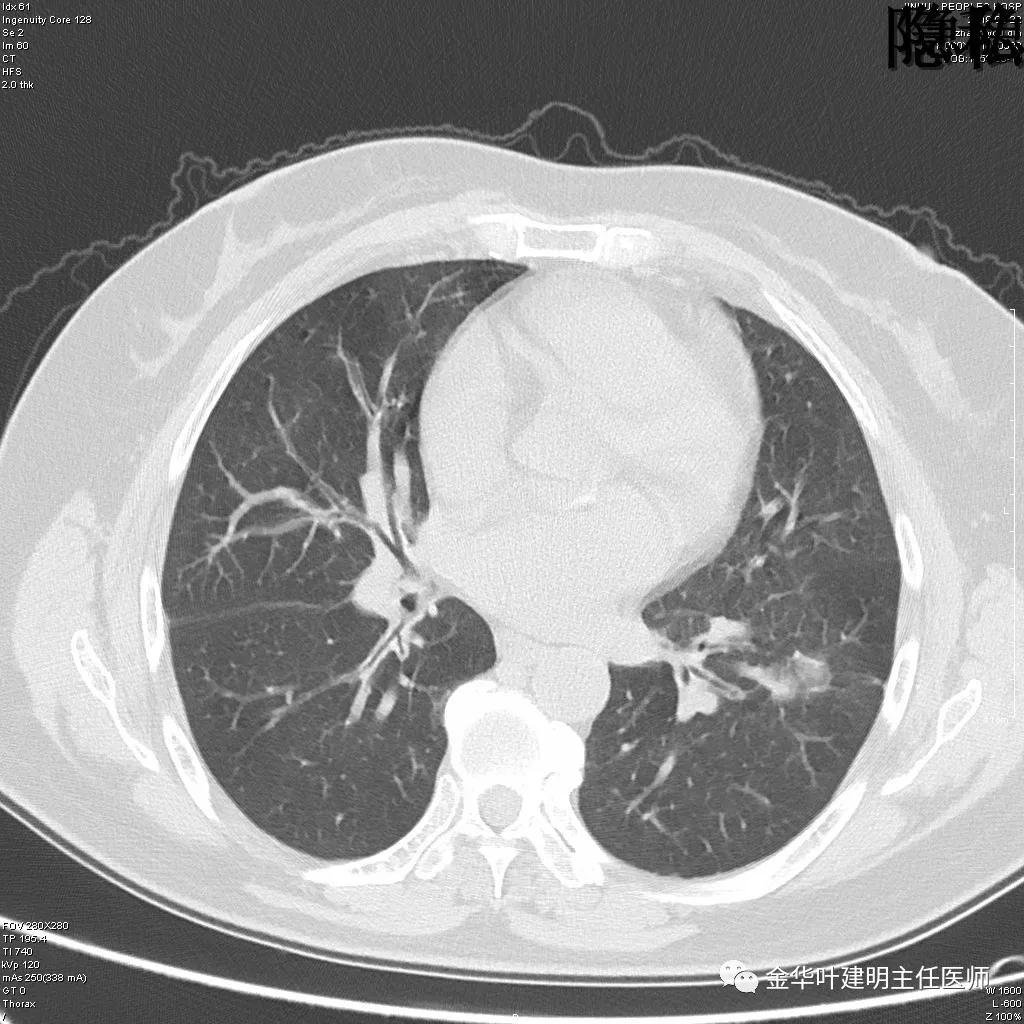

(病例资料2019年)金华的章某,今年60岁,前段时间因为咳嗽,到市区某三甲医院检查,发现她的左肺上叶与左肺下叶都有占位性病变。由于章某有亲戚在我们医院工作,所以在亲戚的指引下,让她来找我。我们予以适当的抗炎治疗,然后复发CT,发现病灶没有任何变化。其中平扫的片子如下:

可见左肺上叶有一占位,是空腔性的,其内有实性密度填充,是比较典型的肺曲菌病的表现,但病灶有点大,长径大于3-4厘米许。

可见左肺下叶比较靠中央的部位也有一病灶,是混合磨玻璃影,偏实性,瘤肺边界清楚,是较为典型的肺癌表现。进一步的靶扫描图像如下:

靶扫描更清晰的显示细节,从影像上看,基本可以断定左下肺的是恶性肿瘤了,而且已经密度较高,长径也在3厘米以上,不能继续观察等待了!